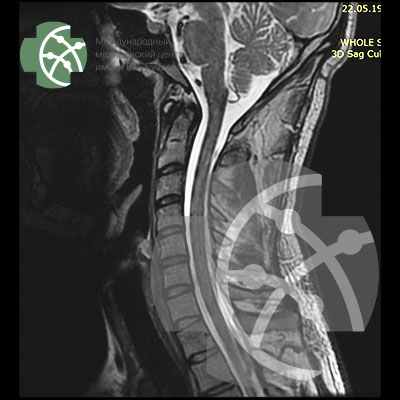

Здравствуйте. Мучают сильные, продолжительные, сдавливающие головные боли правой стороны, с переходом на шею. Длительное время.

Хотела бы узнать, что лучше в таком случае делать. МРТ головного мозга или МРТ сосудов головного мозга.

Головная боль может наблюдаться при различных патологиях. Адекватное обследование определятся после визуального неврологического осмотра, в качестве диагностики скорее всего потребуется МРТ головного мозга, рентгенография шейного отдела позвоночника в 2-х проекциях с функциональными пробами, триплексное сканирование магистральных сосудов шеи (БЦА) с функциональными пробами, РЭГ. Клиника работает ежедневно с 09.00 до 21.00.

Любому человеку знакома головная боль, но если она повторяется подозрительно часто, безусловно, это нельзя оставить без внимания. Мы рекомендуем пациенту с сильными головными болями пройти МРТ головного мозга и его сосудов. В отдельных случаях этого может быть недостаточно, потому как не всегда причина головных болей связана именно с патологией головного мозга. Головные боли могут быть следствием шейного остеохондроза, поэтому наши специалисты дополнительно советуют пройти МРТ шейного отдела позвоночника и сосудов шеи.